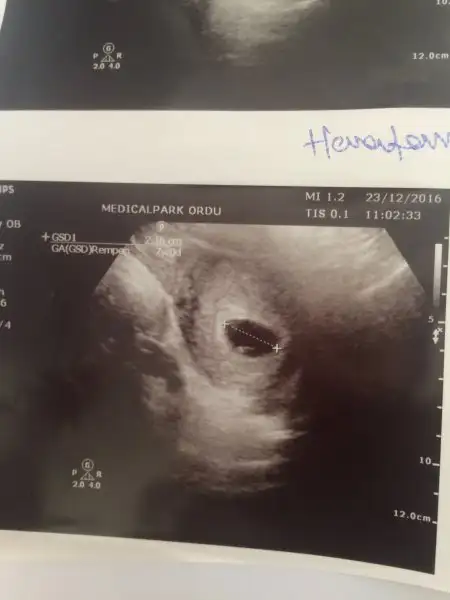

Cinsiyeti belli oldumu canım.keseden sağdaki dgalibaArkadaslar 8 haftalik usg goruntusu tahminde bulunabilirmisiniz ?

Evet canjm belli oldu mesajini yeni gordum kusura bakma erkekmis doktor oyle soylediCinsiyeti belli oldumu canım.keseden sağdaki dgaliba

Saol cnm ya inşlh tşkkür ederimEki Görüntüle 1899208

Can'ım bunada bakarmısınız